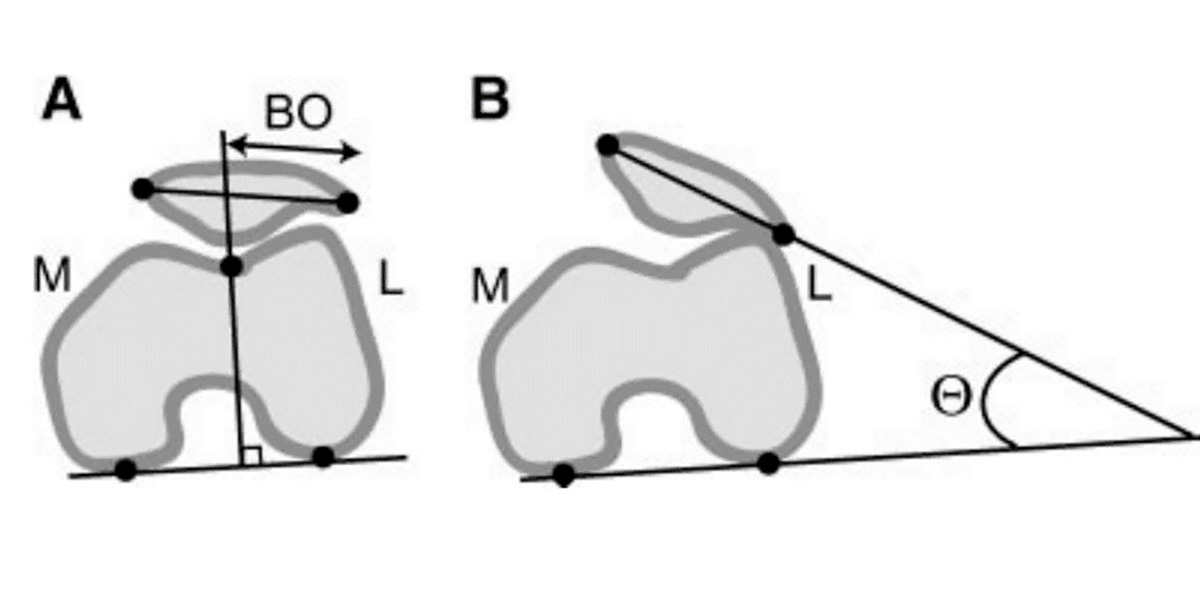

A principal manifestação do joelho é a do desvio patelar:

Este desvio verifica-se quando realizamos exercício físico, por exemplo, no denominado valgo dinâmico funcional, onde o fémur ou a tíbia (ou ambos) rodam internamente e fazem com que o joelho de desloque «para dentro» (adução);

Uma posição na qual não deveria estar, e que aumenta radicalmente a resistência por atrito, degradando a cartilagem.

Figura IV. Representação gráfica de um valgo funcional no joelho.

A articulação do joelho, que está sujeita a esta posição durante muito tempo (por exemplo, os praticantes de desporto), acaba por deslocar a rótula para o exterior, dificultando o controlo muscular sobre a articulação e causando uma grande instabilidade sobre o joelho, o que aumenta o rico de sofrer uma lesão aguda (como uma luxação ou um deslocamento), e/ou crónica (tendinite, desgaste da cartilagem, osteoartrite…).

Esta situação denomina-se de desvio patelar.

Figura V. Representação gráfica do deslocamento patelar na vista frontal (A) e axial (B).